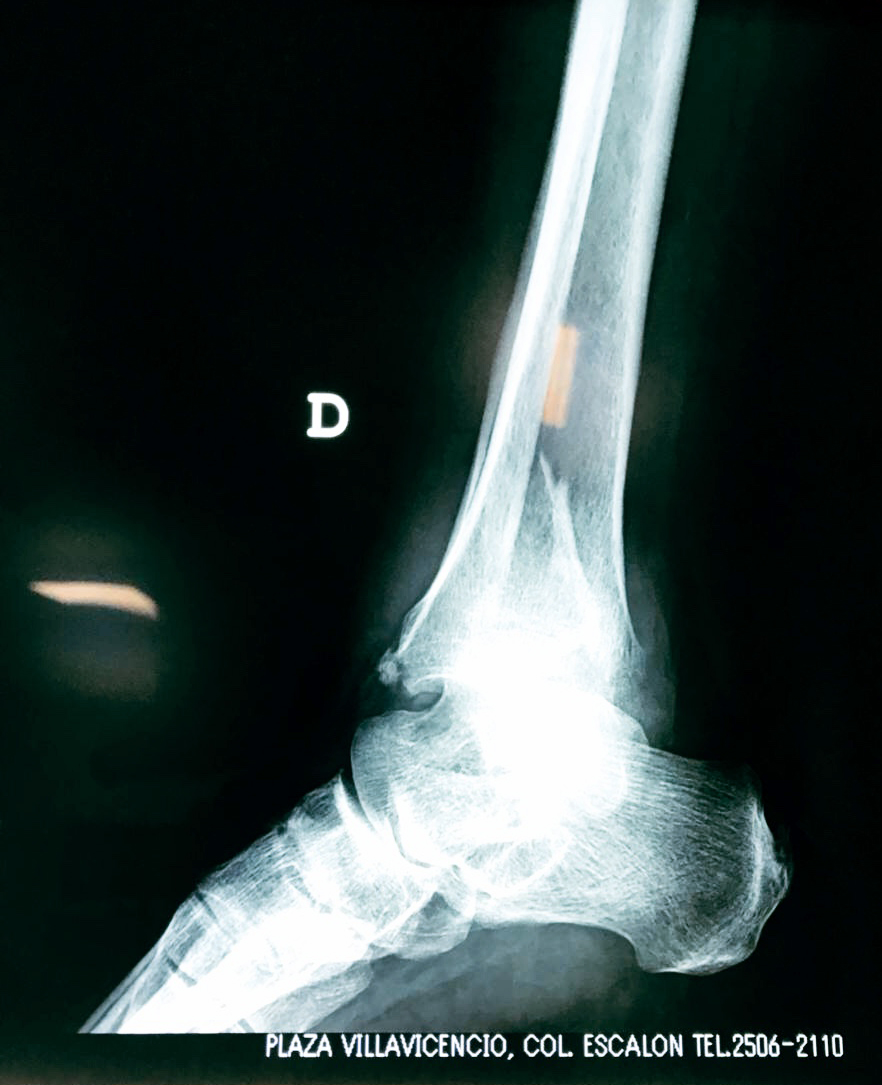

Cuando se necesita cirugía, es probable que esta implique el uso de clavijas de metal, tornillos o placas para sostener los huesos en su lugar mientras la fractura se consolida. Los elementos de soporte pueden ser temporales o permanentes.